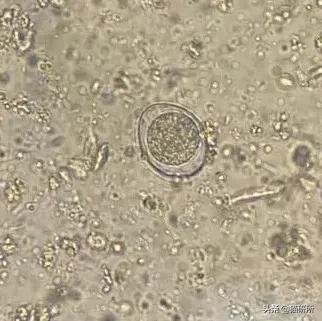

400倍镜下的球虫卵

感染球虫的成猫可能不表现临床症状,但对幼猫,则可能引发较严重的腹泻、出血性的肠炎、脱水等情况,严重的可引发死亡。